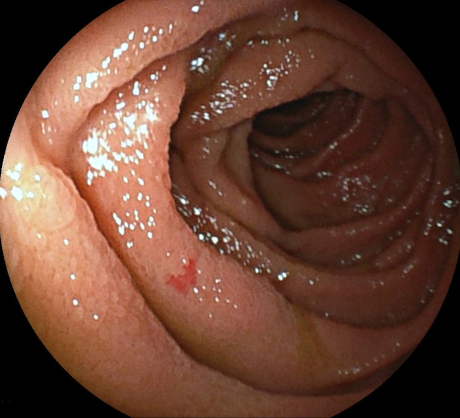

Angiodysplasia is visualised as bright red lesions, 5-10 mm in diameter, with a branching surface network of fine, ectatic blood vessels arising from a central vessel. In hospitalised patients with acute lower gastrointestinal bleeding, the American College of Gastroenterology and European Society of Gastrointestinal Endoscopy recommend a non-urgent inpatient colonoscopy, as re-bleeding may be missed if an urgent colonoscopy is performed.[35][38]

[Figure caption and citation for the preceding image starts]: Endoscopic (device-assisted enteroscopy) image of small bowel angiodysplasiaFrom the personal collection of Dr Elli, Milan, Italy; used with permission [Citation ends].